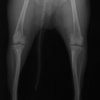

■ 症例22 ポメラニアン 1歳5か月 去勢雄

左後肢の挙上を主訴に来院した。整形学的検査、レントゲン検査より左右の膝蓋骨脱臼(左GradeⅡ〜Ⅲ、右Grade Ⅱ)を認めた。また、脛骨の前方引き出し試験の際に、引き出し兆候は認められないものの、疼痛が認められたため、前十字靭帯の損傷が疑われた。術中における、目視および関節内の操作によって、前十字靭帯の損傷や過伸展といった異常が認められなかったため、膝蓋骨脱臼の整復のみ実施した。手術手技は縫工筋及び内側広筋の解放、脛骨粗面の外側転位、滑車ブロック形造溝術、内外側関節包の縫縮を実施した。本症例は跛行もなく経過良好である。しかし、頸骨高平部の角度(TPA)が 右26.2°、左24.9°であり、解剖学的に前十字靭帯損傷のリスクが高いことから今後の経過に注意が必要である。